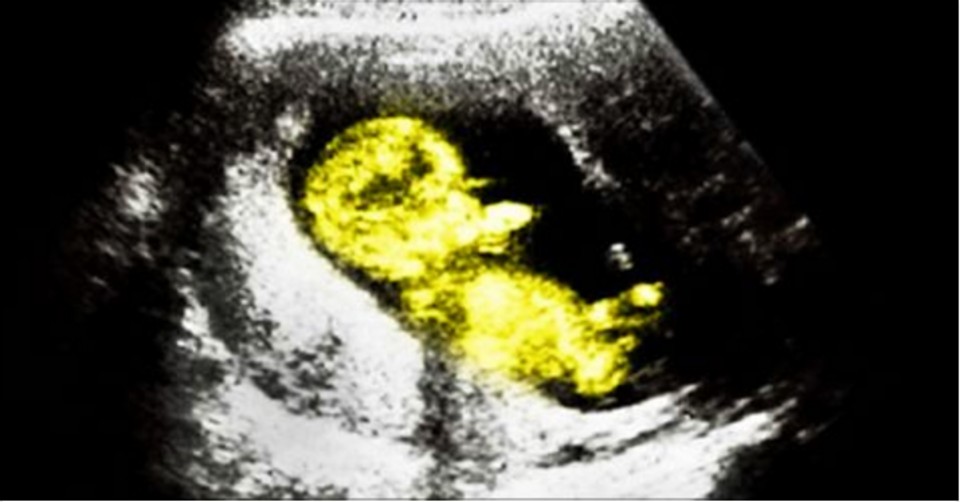

A baby amazed everyone after he was born at just 22 weeks pregnant. The child weighed only 570 grams and was smaller than his mother’s palm.